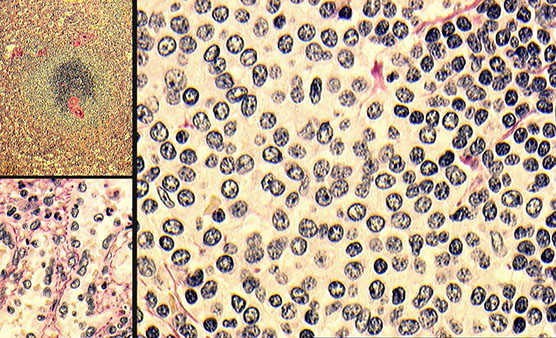

Upper left shows scattered reactive follicles, upper right shows fairly well-differentiated mantle zones, lower left shows aggregates of monocytoid B-cells (small cells) in the paracortical region, and the lower right is a somewhat atypical immunoblastic cells (would stain positive for EBV ISH)

High-powered view of monocytoid B-cells (MBCs) in infectious mono, which have slightly irregular, almost centrocyte-like nuclei with abundant pale cytoplasm and some interspersed neutrophils